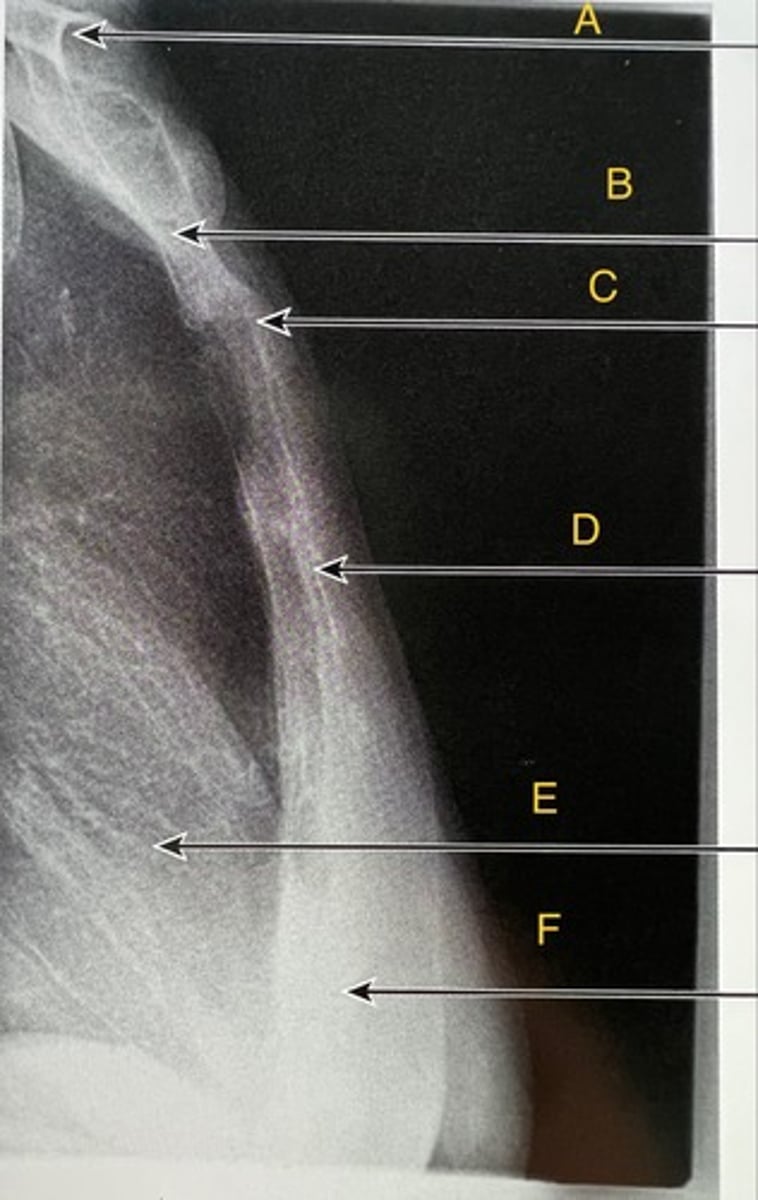

sternoclavicular joint

A.

Trachea

B.

Vertebral body

C.

Heart

D.

Diaphragm

E.

Oblique ribs

What position?